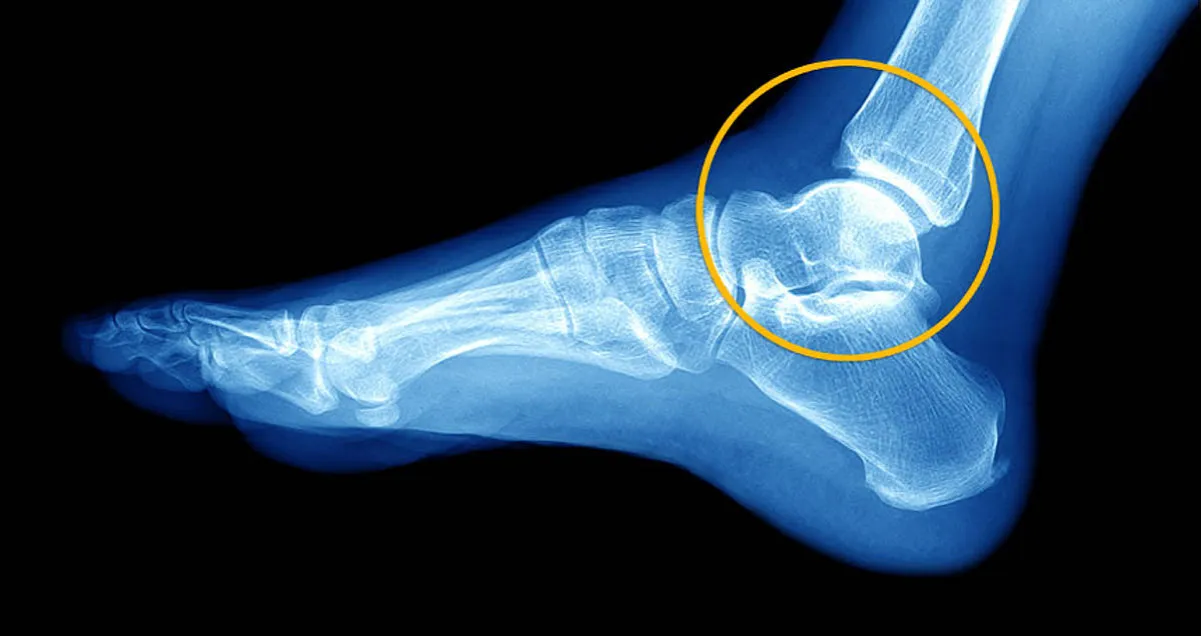

Po skręceniu stawu skokowego często obserwujemy ograniczenie ruchomości stopa nie porusza się tak swobodnie jak zwykle, a próby wykonania pełnego zakresu ruchu są bolesne. To normalna reakcja na uraz. Jednak zupełnie inną sytuacją jest całkowita blokada stawu, gdy nie jesteś w stanie wykonać nawet minimalnego ruchu stopą. Taka blokada może świadczyć o tym, że coś fizycznie uniemożliwia ruch, na przykład przemieszczony fragment kości, duży krwiak wewnątrzstawowy lub bardzo silny skurcz mięśni. To objaw alarmujący, który wymaga pilnej diagnostyki obrazowej, najczęściej rentgenowskiej.

Jeśli po urazie zauważysz, że okolica kostki wygląda nienaturalnie jest wyraźnie zniekształcona, kości wydają się być przemieszczone, a sam staw jest w dziwnej pozycji to jest to bezwzględne wskazanie do natychmiastowej pomocy medycznej. Taka deformacja niemal zawsze świadczy o bardzo poważnym urazie, najczęściej o złamaniu jednej lub więcej kości w okolicy stawu skokowego. W niektórych przypadkach może to być również zwichnięcie stawu. W takiej sytuacji nie próbuj samodzielnie nastawiać kończyny ani czekać, aż ból minie. Należy jak najszybciej unieruchomić kończynę i wezwać pogotowie lub udać się na SOR, ponieważ szybka interwencja jest kluczowa dla prawidłowego leczenia i uniknięcia powikłań.

Rozróżnienie skręcenia od złamania bywa trudne nawet dla doświadczonego oka, dlatego kluczowe jest badanie obrazowe. Istnieją jednak pewne objawy, które mogą silniej sugerować złamanie kości w okolicy stawu skokowego:

- Widoczna deformacja: Jak już wspomniałem, widoczne zniekształcenie, nienaturalne ułożenie stopy lub wyczuwalne przemieszczenie kości to bardzo silne wskaźniki złamania.

- Ból punktowy: Jeśli ból jest bardzo silny i wyraźnie zlokalizowany w jednym, konkretnym punkcie kości (np. na kostce bocznej lub przyśrodkowej), a nie rozlany w całym stawie, może to wskazywać na złamanie.

Oprócz złamań, w okolicy stawu skokowego mogą wystąpić również inne urazy, które dają podobne objawy do skręcenia. Przykładem jest uszkodzenie ścięgien, takich jak ścięgno Achillesa (choć to uraz zazwyczaj bardziej charakterystyczny i zlokalizowany z tyłu pięty) czy ścięgna strzałkowe. Ich naciągnięcie lub zerwanie również objawia się bólem, obrzękiem i ograniczeniem ruchomości. Czasami dochodzi także do uszkodzeń chrząstki stawowej lub innych drobnych struktur wewnątrz stawu, które nie są widoczne na standardowym zdjęciu RTG. Dlatego tak istotna jest dokładna diagnostyka lekarska, która może obejmować nie tylko RTG, ale także USG, a w niektórych przypadkach rezonans magnetyczny (MRI), aby wykluczyć wszystkie możliwe "ukryte" kontuzje i zapewnić prawidłowe leczenie.